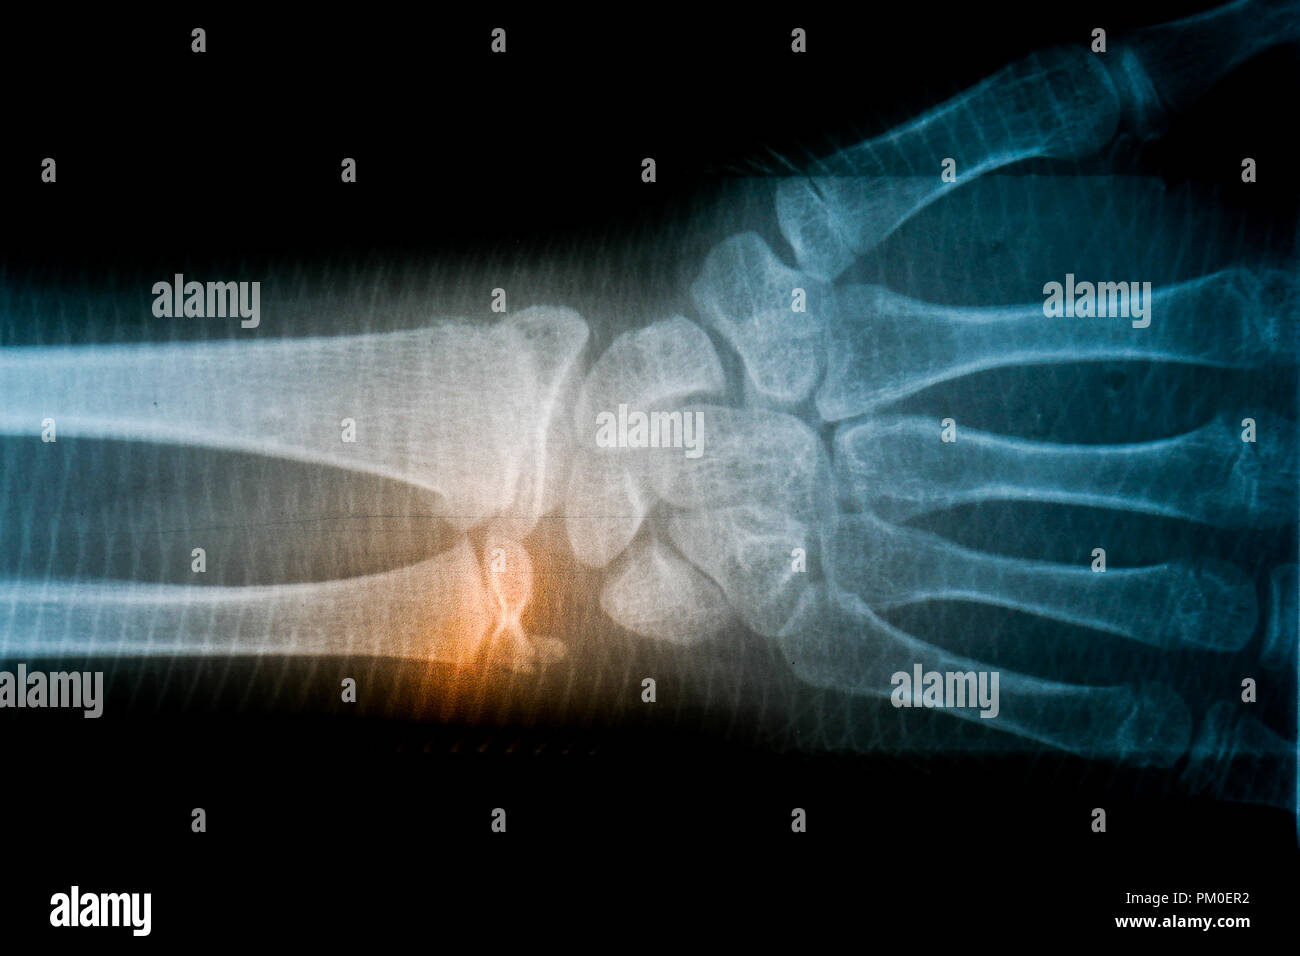

Film Xray Radiograph Show Human Anatomy Stock Photo Edit

Film Xray Radiograph Show Human Anatomy Stock Photo Edit

X Ray Film Skeleton Human Arm Health Medical Anatomy Body

X Ray Film Skeleton Human Arm Health Medical Anatomy Body

X Ray Film Skeleton Human Arm Health Medical Anatomy Body

X Ray Film Skeleton Human Arm Health Medical Anatomy Body

X Ray Film Skeleton Human Arm Health Medical Anatomy Body

X Ray Film Skeleton Human Arm Health Medical Anatomy Body